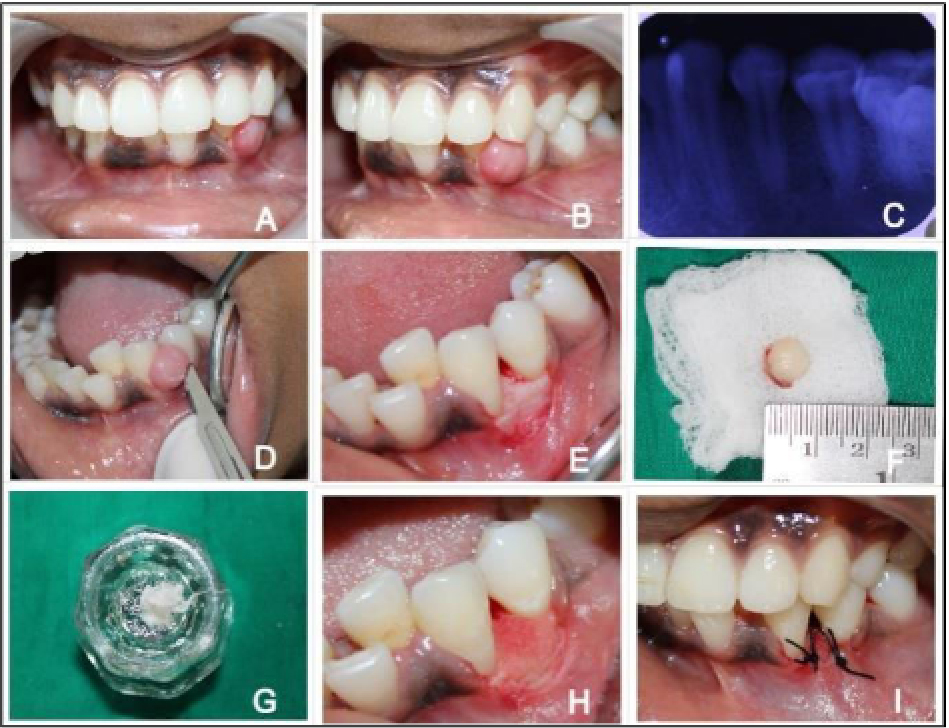

Hemocoll fibres is intended for the surgical procedures as an adjunct to hemostasis when control of bleeding by ligature or conventional procedures is ineffective or impractical includes: extraction and biopsy sites